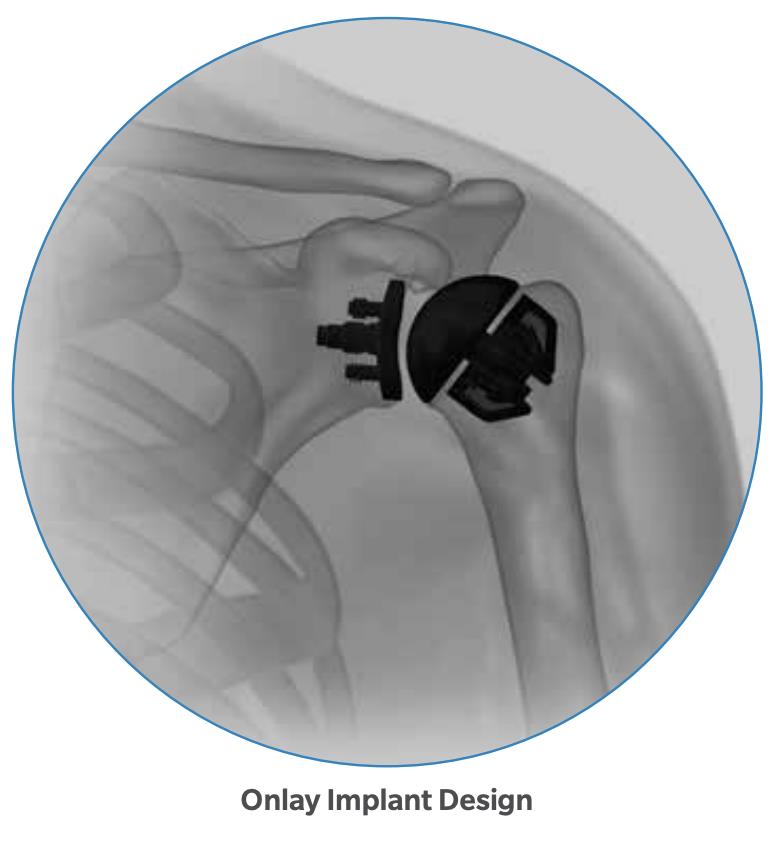

Summary The OsseoFit™ Stemless Shoulder System is indicated for anatomic total shoulder arthroplasty in patients where a bone-sparing, stemless solution is desired to maximize humeral fixation. It achieves this through OsseoTi® Porous Metal Technology and a site-specific fin design that creates a stable, biological press-fit while simplifying the surgical workflow with integrated suture holes. This system addresses a wide variety of patient anatomies using its versatile inlay and onlay size options. Indications Indications osteoarthritis indicated for anatomic total shoulder applications Contraindications local/systemic infection, sepsis, and osteomyelitis active local or systemic infection sepsis osteomyelitis inadequate humeral bone inadequate bone may lead to poor implant fixation large metaphyseal cysts may compromise stemless fixation irreparable cuff tear rotator cuff must be functionally reconstructable for anatomic total shoulder arthroplasty revision of any stemmed or stemless prothesis contraindicated for revision of any stemmed or stemless prosthesis Anatomy Osteology humeral head anatomic neck greater tuberosity lesser tuberosity bicipital groove metaphyseal cancellous bone Muscles deltoid forms the lateral border of the deltopectoral interval pectoralis major forms the medial border of the deltopectoral interval subscapularis released and repaired according to surgeon preference Ligaments glenohumeral capsule is released as needed to expose the humeral head and glenoid coracohumeral ligament contributes to rotator interval constraint superior, middle, and inferior glenohumeral ligaments contribute to anterior stability transverse humeral ligament overlies the bicipital groove Nerves axillary nerve courses inferior to the subscapularis and around the lateral humerus must be protected musculocutaneous nerve lies medial to the coracobrachialis and conjoint tendon suprascapular nerve is at risk with aggressive posterior-superior glenoid exposure Blood supply anterior and posterior humeral circumflex arteries arcuate artery is a terminal branch of the anterior humeral circumflex system suprascapular and circumflex scapular vessels Preoperative Planning X-rays A/P, scapular Y and axillary views evaluate bony anatomy, humeral head position, glenoid wear, deformity, and acquired bone loss use x-ray templates to estimate stemless humeral implant size assess whether an anatomic total shoulder reconstruction is appropriate CT assess bone quality and identify any humeral bone tissues use to assess bone quality and identify humeral bone issues that may affect implant selection evaluate metaphyseal bone stock, cysts, avascular necrosis, deformity, and cortical support Approach Extended deltopectoral anterior incision with an optional biceps tenodesis beginning immediately above the coracoid process and extending distally and laterally, following deltopectoral groove along the anterior border of the deltoid Technique Humeral head resection expose the humeral head and identify anatomic neck landmarks fixed-angle resection targets 135° inclination and 30° retroversion select left- or right-specific extramedullary resection guide align the guide post with the humeral shaft for fixed-angle resection align the 30° version rod with the forearm flexed at 90° place pins to define version and inclination and to stabilize the cutting surface resect the humeral head through the far side of the humeral head adjust the resection with the guide or calcar planer if needed assess bone quality with direct pressure perpendicular to the resected surface consider stemmed humeral fixation if cancellous bone is easily depressed or primary stability is questionable Humeral protection during glenoid preparation select the humeral resection cover that most closely fits the resected surface prepare the glenoid using the appropriate compatible glenoid technique remove the humeral resection cover before humeral sizing Humeral sizing place the humeral sizer onto the resection surface select the size intended to optimize cancellous bone fixation without violating the inner cortical rim orient the sizer so the bicipital groove bisects the superior and anterior fins insert the central Steinmann pin through the center of the sizer and through the lateral cortex avoid deep lateral cortical penetration to reduce risk to the axillary nerve place a lateral humeral retractor as needed to protect the axillary nerve confirm sizing after any additional planing Humeral bone preparation (boss reaming) ream until the boss reamer bottoms out on the resected surface ream over the central Steinmann pin with the boss reamer protect the lateral humerus and axillary nerve with a retractor remove the boss reamer while leaving the central Steinmann pin in place Humeral bone preparation (broaching) select the reference foot based on implant size select the broach that corresponds to the humeral sizer align the broach superior fin with the superior indicator line on the broach inserter slide the assembly over the central Steinmann pin until the broach contacts the resection surface remove the inserter-reference foot assembly and central Steinmann pin perform broach stability testing consider stemmed humeral fixation if the broach is unstable Humeral head trialing determine humeral head diameter and height using the humeral head sizing template or the resected humeral head seat the head trial assembly into the broach rotate the trial assembly with the hex driver to assess coverage of the resection surface confirm alignment with the anterior and posterior borders of the humeral resection increase offset if the head trial does not cover one side of the resection decrease offset if the head trial overhangs the resected bone reduce the joint and perform trial range of motion record the final offset letter or interval on the proximal humerus remove and disassemble the head trial assembly Implant insertion remove the broach with the slap hammer while maintaining an on-axis trajectory use the same reference foot size used for broach insertion select the implant size corresponding to the final broach and operative side slide the reference foot down until it uniformly contacts the resection surface confirm superior fin markings on reference foot, implant, and bone are aligned disengage the inserter-reference foot assembly with axial traction and slight rotational force as needed onlay implant center boss is slightly proud of the resection surface, with fin top surfaces flush inlay implant sits below the resection surface Humeral head implantation select the final humeral head implant matching the trial diameter and height use the offset letter or interval determined during trialing place the humeral head into the concave surface of the impactor base on a rigid sterile table impact the adapter into the humeral head with the disposable impactor using a mallet, strike the head impactor at least twice until the humeral head is flush with the resection visually confirm uniform seating consider implant subsidence and stemmed fixation if no pre-impaction gap is present Technical specifications Implant design anatomically shaped asymmetric anchor design designed to match natural asymmetric humeral anatomy designed to maximize cancellous bone fit and help avoid cortical impingement six-fin configuration with progressive tapered wedge design fins are designed for press-fit insertion each fin contains a fully porous window anterior suture holes are present for subscapularis repair Porous technology OsseoTi® Porous Metal Technology is used in the stemless implant porous architecture is designed to mimic human cancellous bone design incorporates a fully porous 3D printed OsseoTi® lattice within a titanium framework Technical specifications OsseoFit Onlay Anchor Implant Side Size Left 1, 2, 3, 4, 5 Right 1, 2, 3, 4, 5 OsseoFit Inlay Anchor Implant Side Size Left 1, 2, 3, 4, 5 Right 1, 2, 3, 4, 5 OsseoFit Humeral Head Adapter